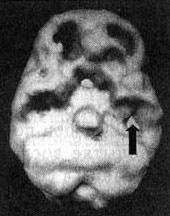

Выступая в качестве судебного психиатра-консультанта, я согласился с клиническим диагнозом СДВ, а на основании постоянной агрессивности Брэдли и нарушений на ЭЭГ заподозрил и дисфункцию левой височной доли. Я назначил ему сканирование SPECT при попытке сосредоточиться без лекарства и попытке сосредоточиться с Ritalin. Результаты сканирования в состоянии покоя выявили умеренное снижение активности левой части префронтальной коры и левой височной доли. При попытке сосредоточиться наблюдалось выраженное угнетение функции префронтальной коры (характерное нарушение при СДВ) и обеих височных долей. Третье сканирование мы провели через час после того, как Брэдли принял 15 мг Ritalin. На этот раз мы увидели выраженную активизацию префронтальной коры и обеих височных долей, хотя в левой височной доле небольшое снижение активности все еще сохранялось.

Мозг Брэдли

Трехмерное изображение поверхности, вид снизу.

Снимок мозга при попытке Брэдли сосредоточиться (без лекарственного препарата); обратите внимание на снижение активности в левой префронтальной коре и левой височной доле (стрелка).